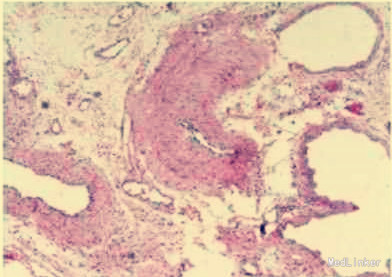

诊断:1.低血容量性休克;2.腹痛伴黑便查因;3.门静脉高压? 治疗:在积极抗休克的同时,决定行剖腹探查术。术中,胃食管下段区域及腹膜后曲张静脉丛未见出血,一段小肠与腹壁形成粘连,粘连处有一支发自肠系膜的曲张静脉穿经小肠,再进入腹壁。该段肠腔中充满淤血,其近端肠腔未发现血液,而远端集聚大量血液。术中肠镜检查发现胃至小肠末端区域血管扩张,但均无出血,小肠与腹壁粘连处曲张静脉有出血点。在结扎曲张静脉、切除出血肠段后,患者血压快速回升。

门静脉高压所致静脉曲张常发生在食管下段、胃部或直肠,极少数可发生在消化道其他位置。消化道外异位曲张静脉则非常罕见。1项纳入169例异位曲张静脉出血的研究显示,17%的异位曲张静脉位于十二指肠,17%位于空、回肠,14%位于结肠,8%位于直肠,9%位于腹膜。对于腹痛黑便的患者患者要小心门静脉高压的可能,尽早针对性治疗。